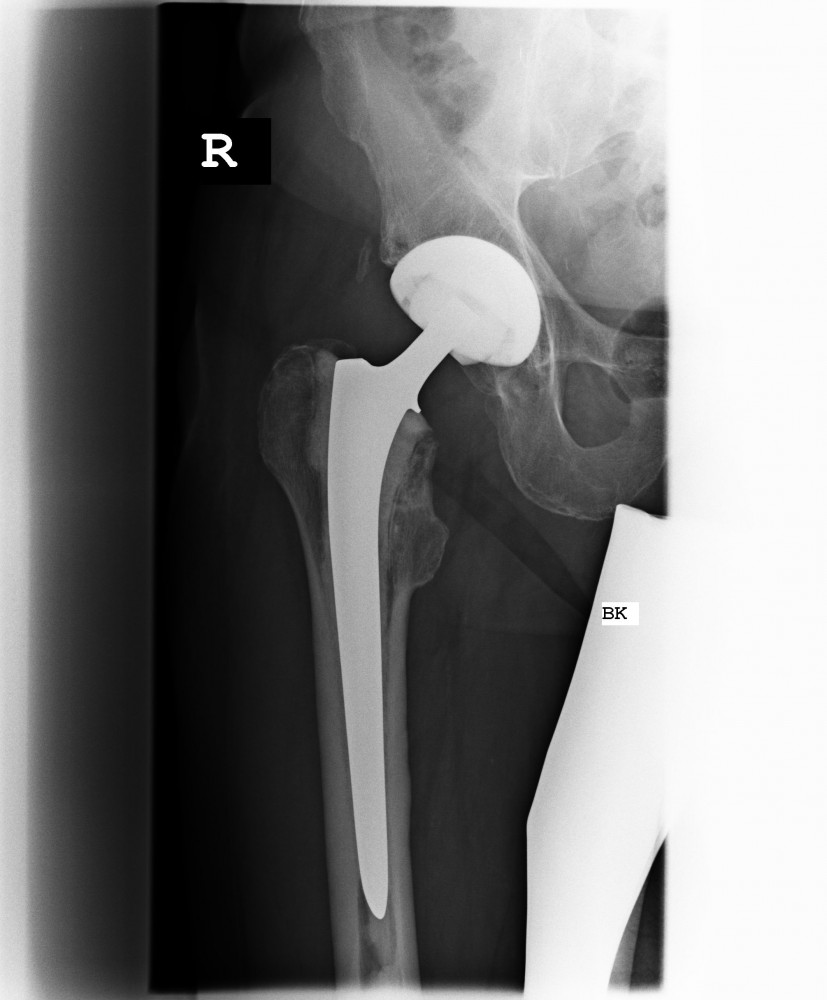

Anatomische Geradschaftprothese

Um bei etwas schlechteren Knochenverhältnissen eine gute Verankerung zu gewährleisten, kombiniert man in diesem Implantat die Vorzüge der klassischen Geradschaftprothese und der anatomischen Kurzschaftprothese. Das heißt, es wird knochensparend implantiert und aufgrund des längeren Schaftes eine gute Verankerung erreicht. Sollte eine Osteoporose vorliegen, kann dieses Prothesendesign auch zementiert eingebracht werden.